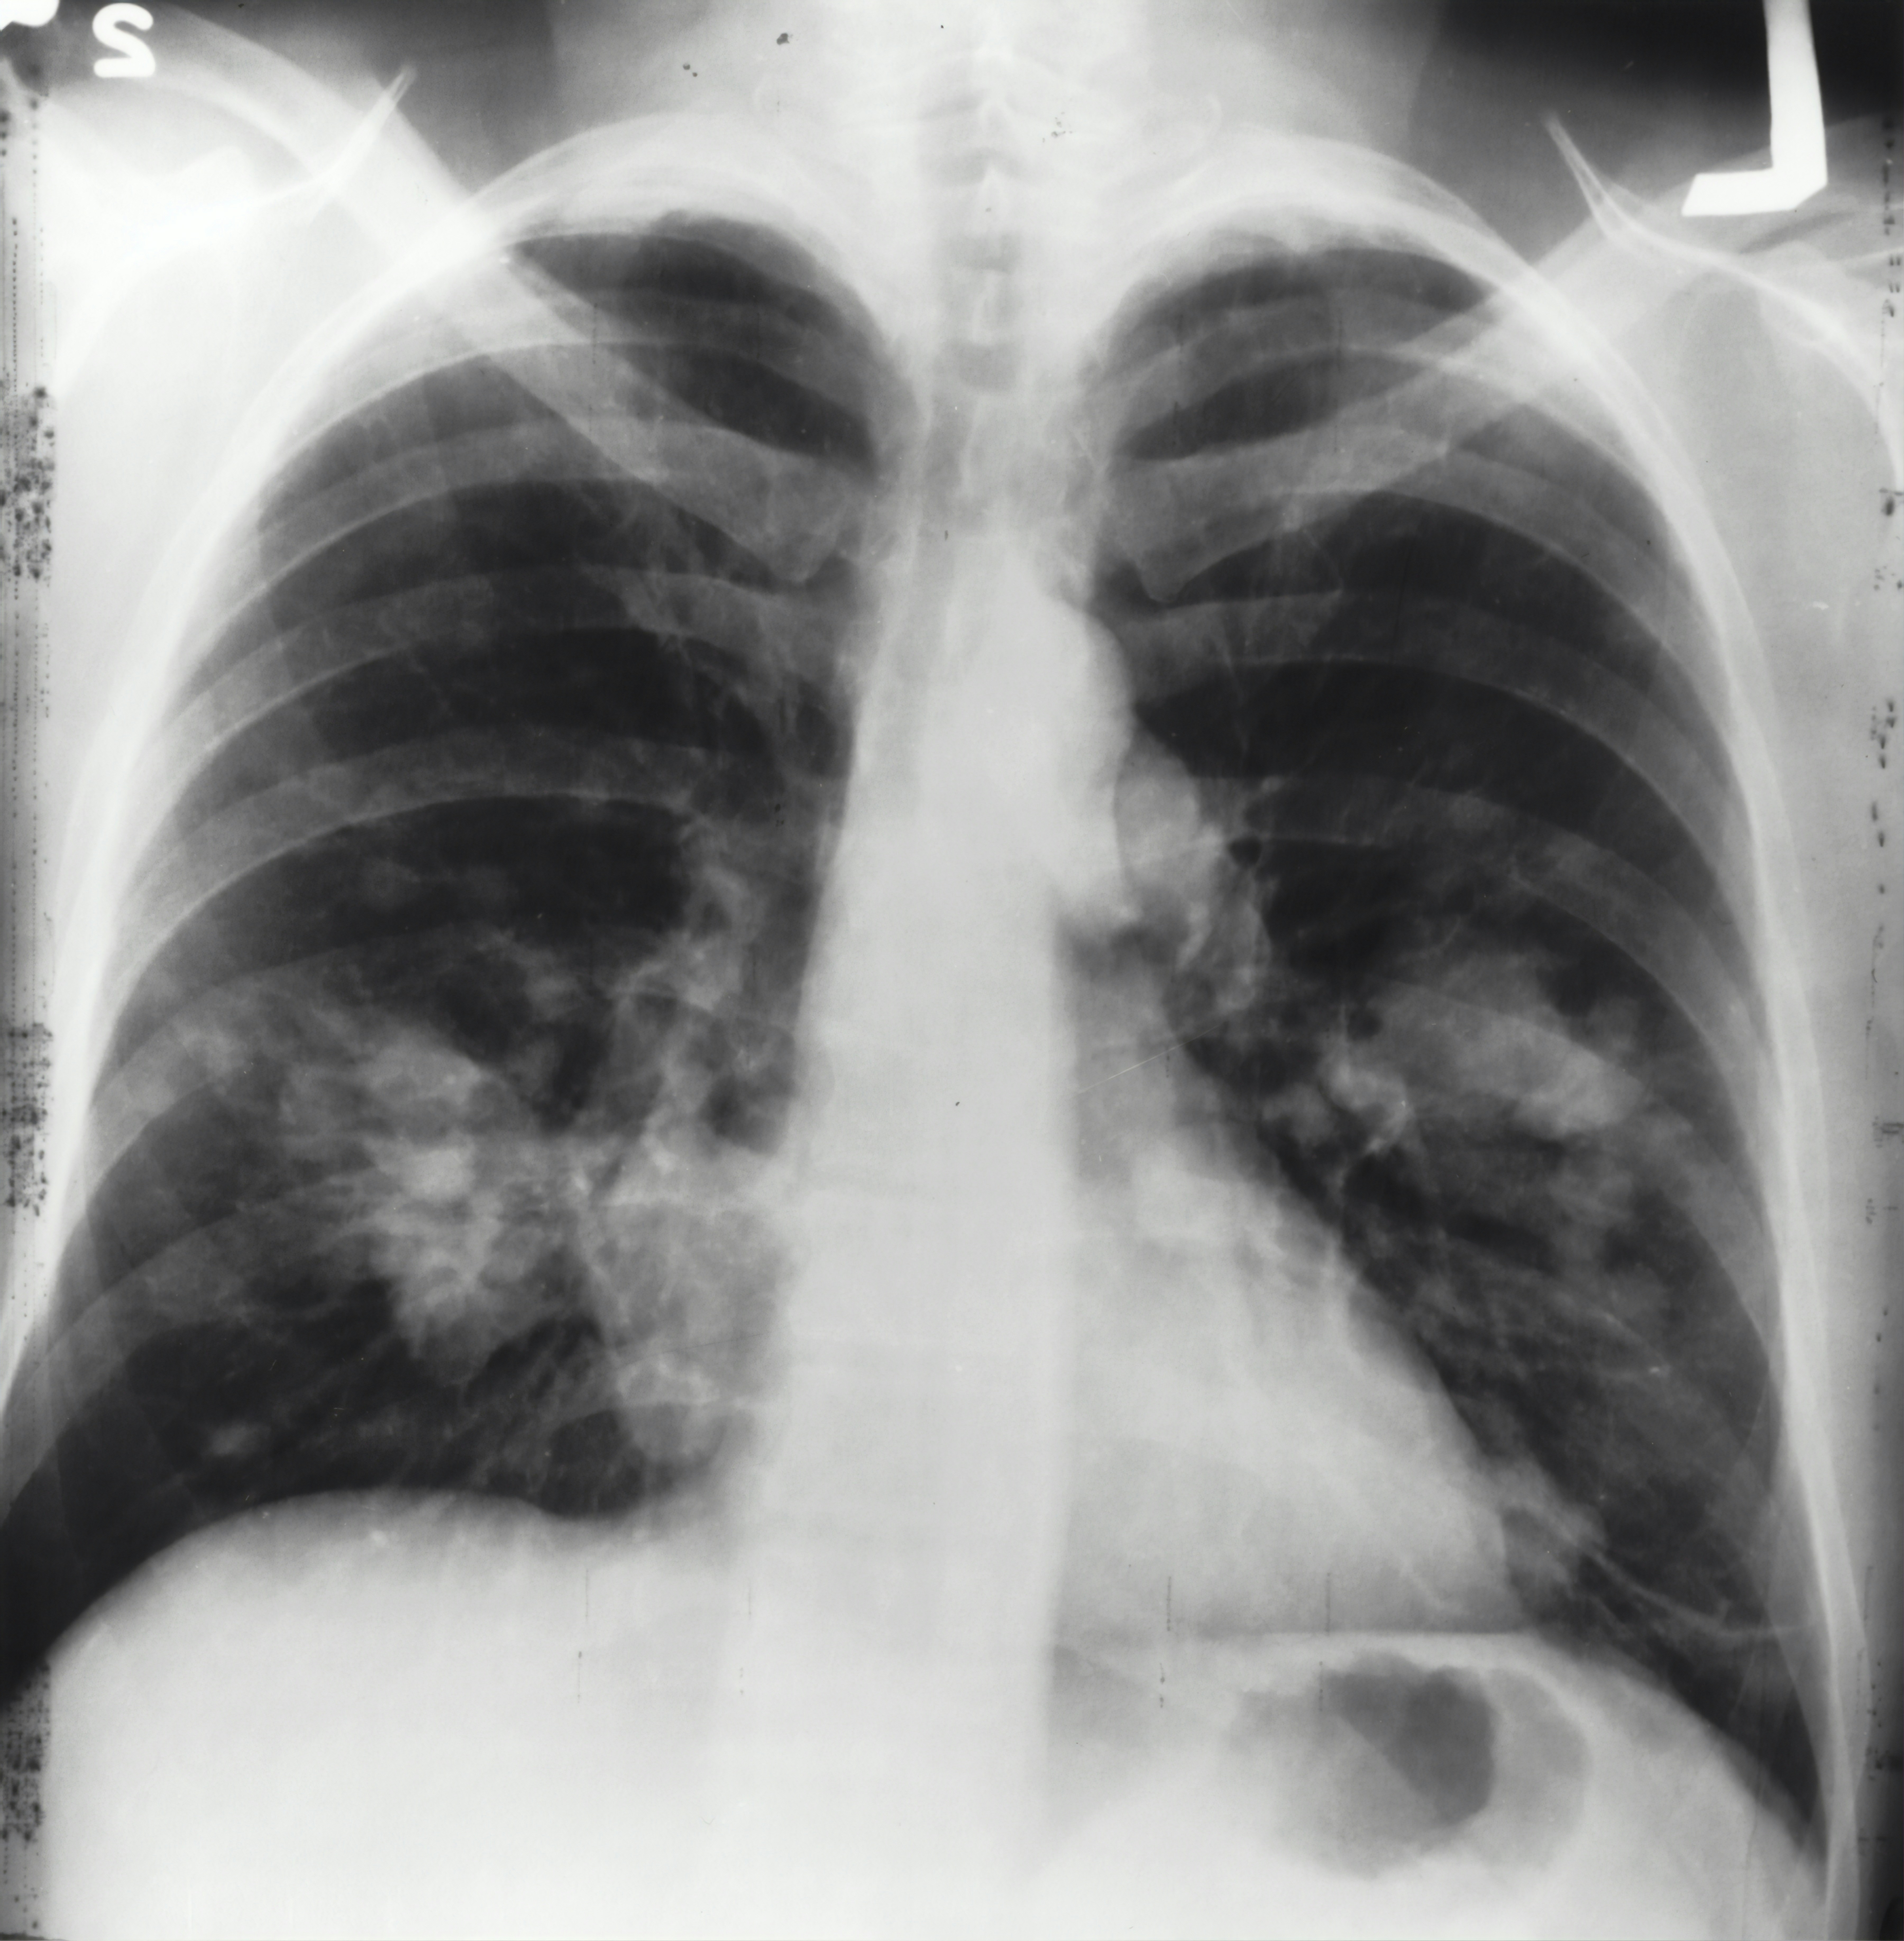

Immunotherapy can help increasing the life span of people having non-small cell lung carcinoma (NSCLC). The therapy improves the immunosystem which can then better act against the cancer cells. One of these immunotherapy agents is pembrolizumab. This substance show great results and studies, however, it is very expensive and can have severe side effects. Furthermore, it is not certain whether the therapy has a beneficial effect for the patient despite the fit of the therapy to the type of lung cancer.

In this study, the Life Science Trace Detection Laboratory will perform untargeted breath profiling on lung cancer patients using prembolizumab therapy. In parallel, an eNose (SpiroNose) will be used for rapid screening. The results from the untargeted screening will be used to validate the findings with the SpiroNose and gain more understanding why certain patients respond to the therapy and other not.